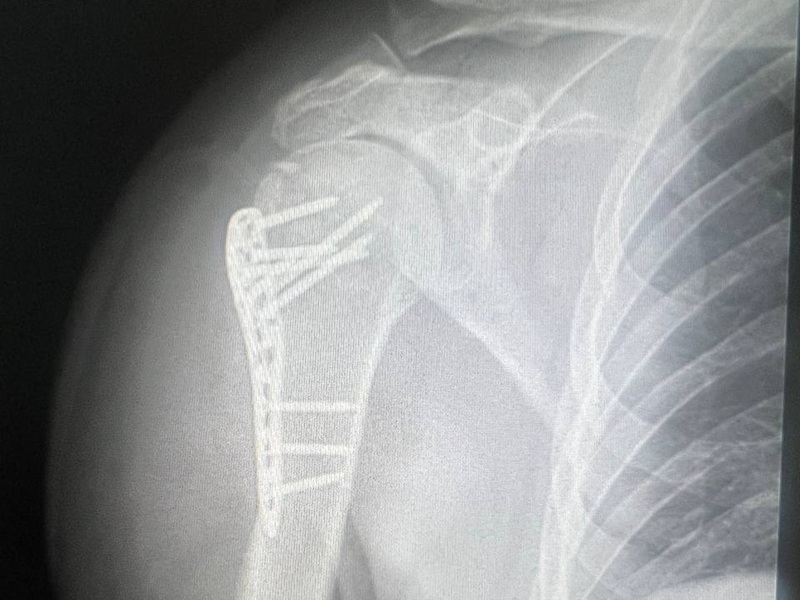

Остеосинтез плеча вивих ДО-ПІСЛЯ: